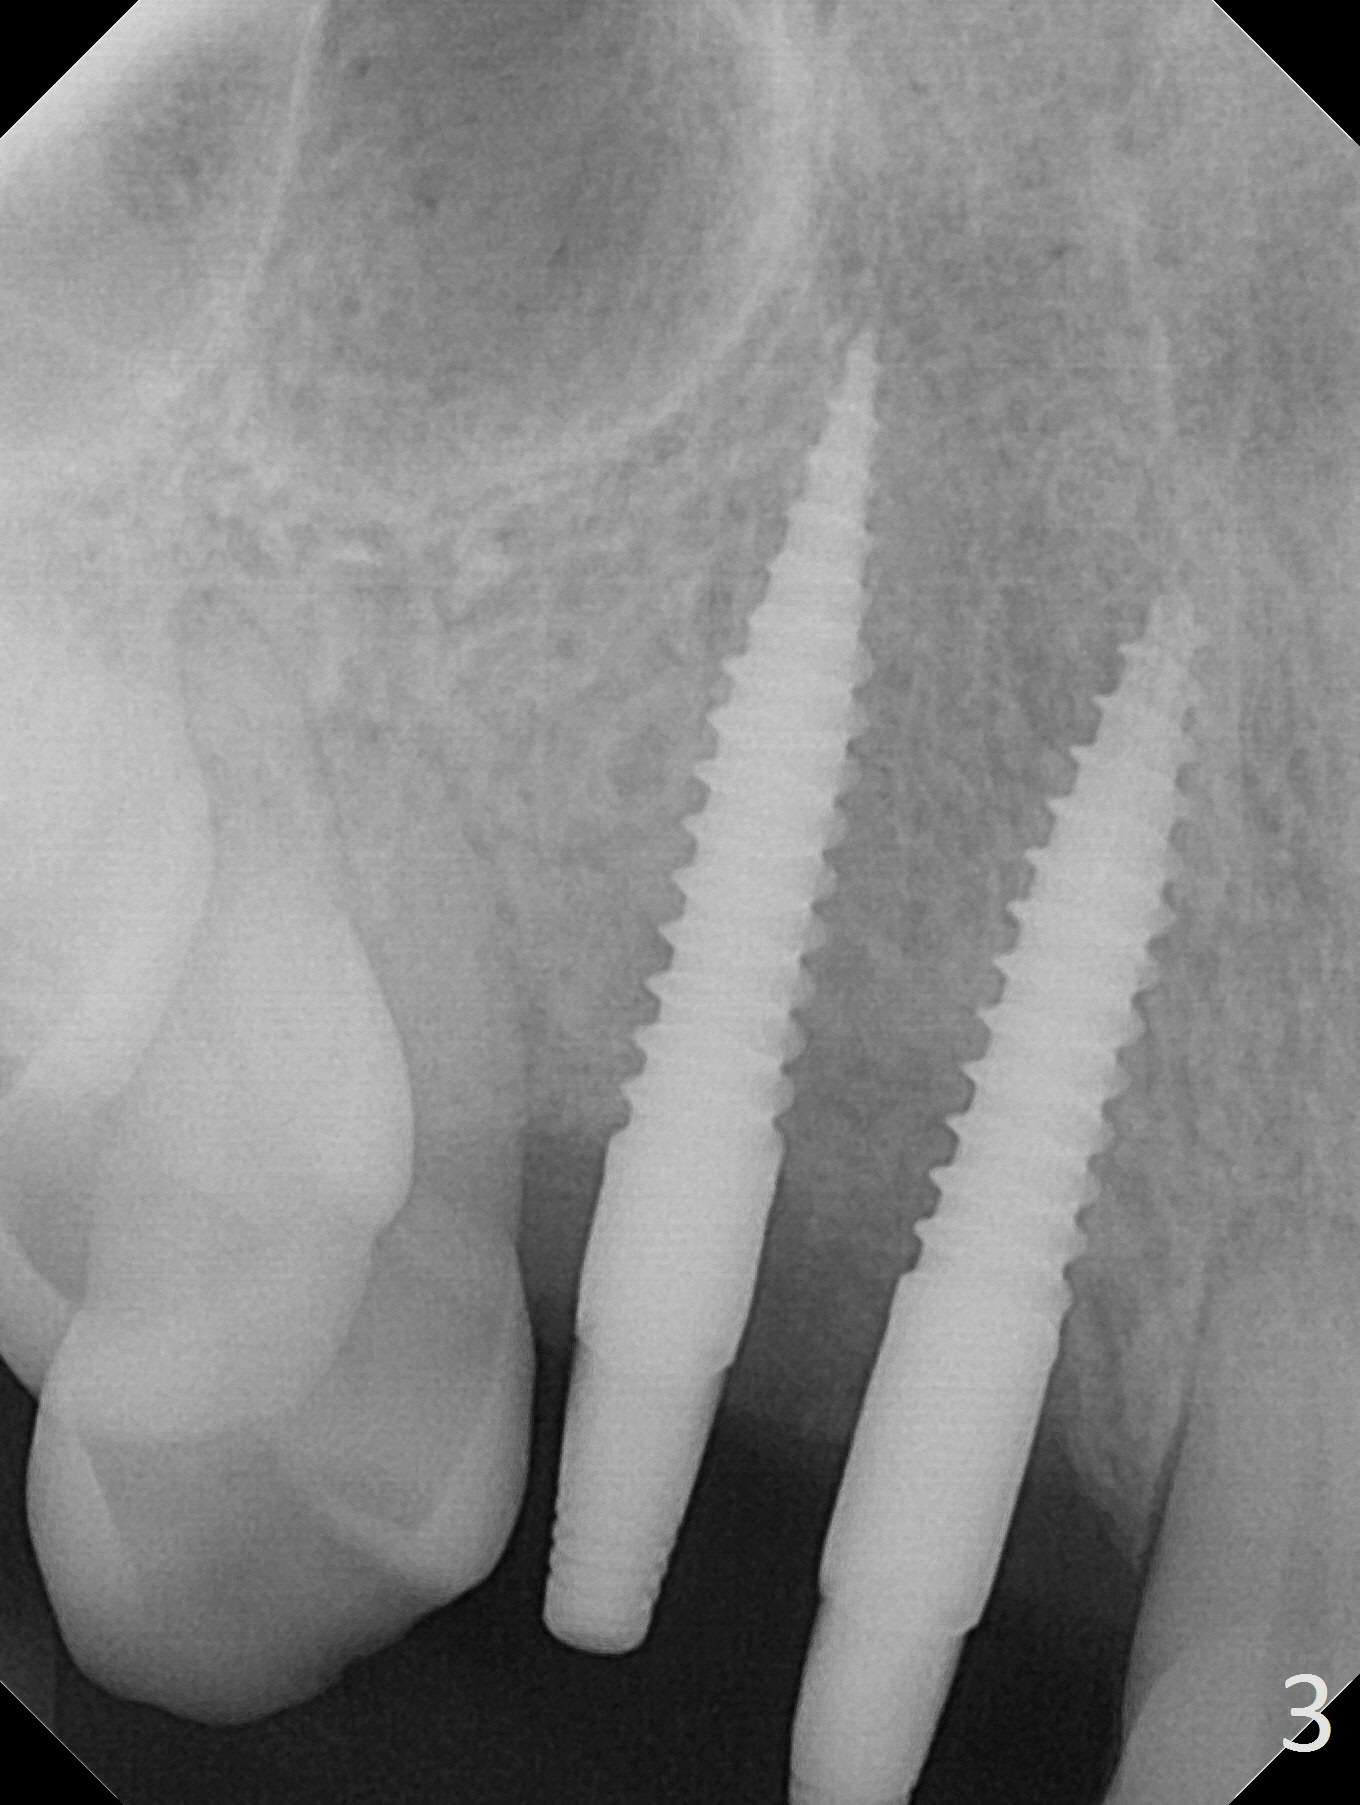

There is no bone loss 3 months postop (Fig.3). After reprep (Fig.4), shades are selected for the final crowns (Fig.5). Before crown cementation at #6 and 7, the patient notes asymmetry with the teeth on the other side (Fig.6). Our concerns are the lack of the papilla distal to #6 (Fig.7 * (multiple modification of provisional needed)) and slight inflammation due to insufficient oral hygiene (^).